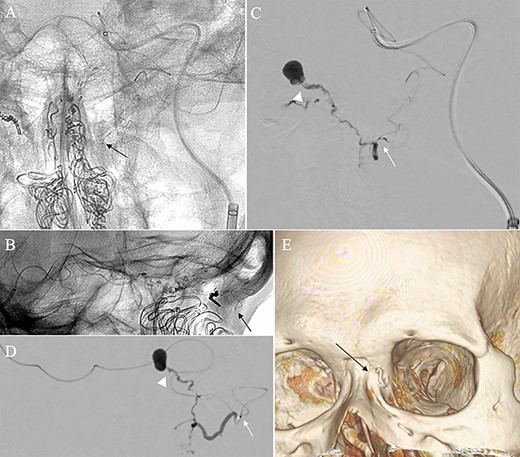

A patient in their 70s with extracranial lymphoma was incidentally found to have ACF–dAVF via head computed tomography and magnetic resonance angiography. Digital subtraction angiography (DSA) confirmed ACF–dAVF with multiple feeding branches, arising from bilateral OphAs, distal IMAs and the left middle meningeal artery (MMA), with cortical venous reflex (Borden type III, Cognard type IV) (Fig. 1). At the patient’s request, we chose endovascular, rather than surgical, treatment. We injected a 20% N-butyl-2-cyanoacrylate (NBCA)–lipiodol mixture into the fistula through bilateral ethmoidal arteries and the left MMA after we placed coils at the terminal branch of the right OphA. However, we could not achieve full penetration into the fistulous connections because of pressure secondary to high flow from the IMA branches, which resulted in incomplete obliteration (Fig. 1). Four months later, we repeated TAE by temporarily reducing nasal blood flow by inserting gauze infiltrated with xylocaine and epinephrine into the nasal cavities. After introducing the guiding catheter, an endonasal surgeon inserted X-ray-detectable surgical gauze infiltrated with 1% xylocaine and epinephrine (1:10 000) into bilateral nasal cavities using a nasal speculum, while paying full attention to avoid damage to the nasal mucosa. Then, we confirmed that the gauzes were placed in appropriate locations in the upper nasal cavity under fluoroscopic guidance. Immediately after insertion, we were able to confirm decreased blood flow from the IMA using DSA (Fig. 2). After this procedure, we navigated a DeFrictor Nano Catheter (Medico’s Hirata, Osaka, Japan) into the terminal branch of the OphA, which was connected to the dorsal nasal artery. Even though there was still a distance from the tip of the microcatheter to the shunt pouch, the NBCA reached the shunt point and penetrated the venous portion (Fig. 3). Follow-up DSA demonstrated complete obliteration of the ACF–dAVF, and blood flow in the nasal mucosa from the IMA branches recovered normally (Fig. 4).

(A) DSA, anteroposterior view, showing complete obliteration of the anterior cranial fossa–dural arteriovenous fistula. (B and C) DSA, anteroposterior view, showing restored blood flow from the internal maxillary artery branches.